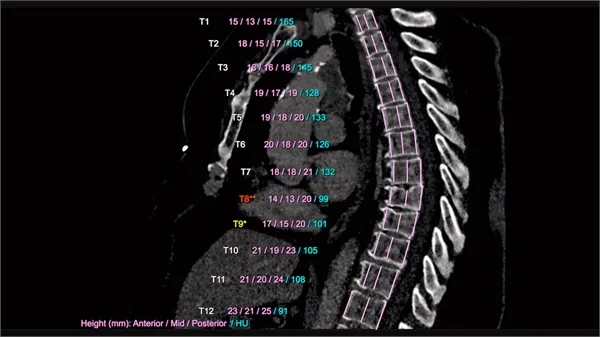

La imagen muestra un escáner de IA de una columna vertebral. Se mide y compara la altura de cada vértebra. El AI-Rad Companion Chest CT de Siemens Healthineers procesa automáticamente estas mediciones y marca las anormalidades con un código de colores fácil de entender. Las desviaciones se resaltan en rojo y amarillo, y se informa de la densidad ósea. (Crédito: Siemens Healthineers vía Klinikum Nürnberg, Nuremberg, Alemania)